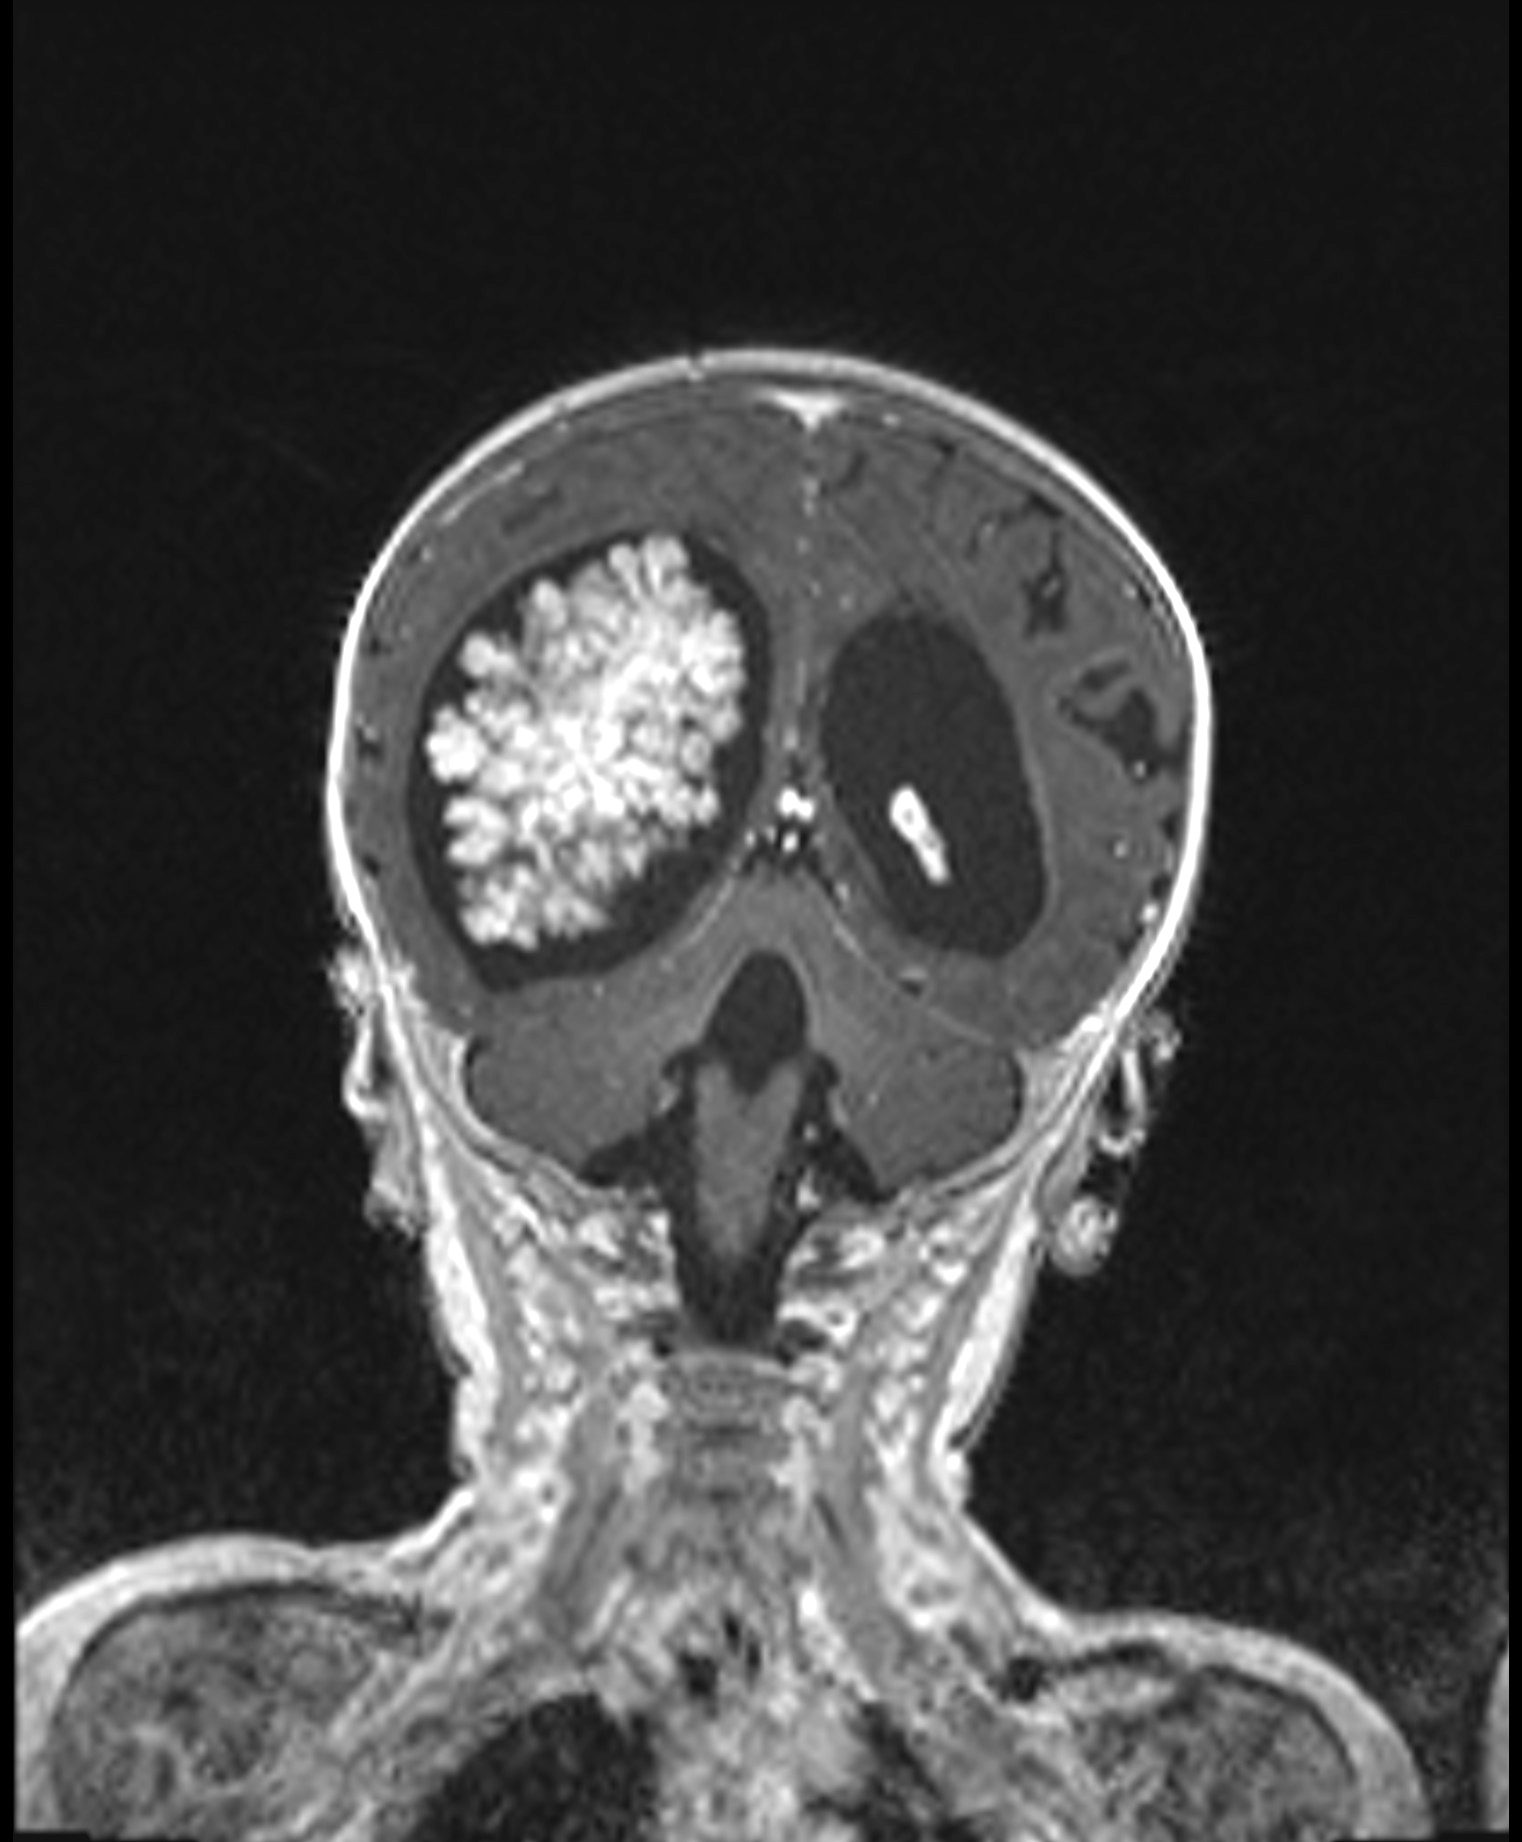

Radiology description

- Intraventricular papillary or lobulated lesions on MRI; hypo or isointense on T1, hyper or isointense on T2 and enhanced in postcontrast imaging (Cancer Imaging 2019;19:17)